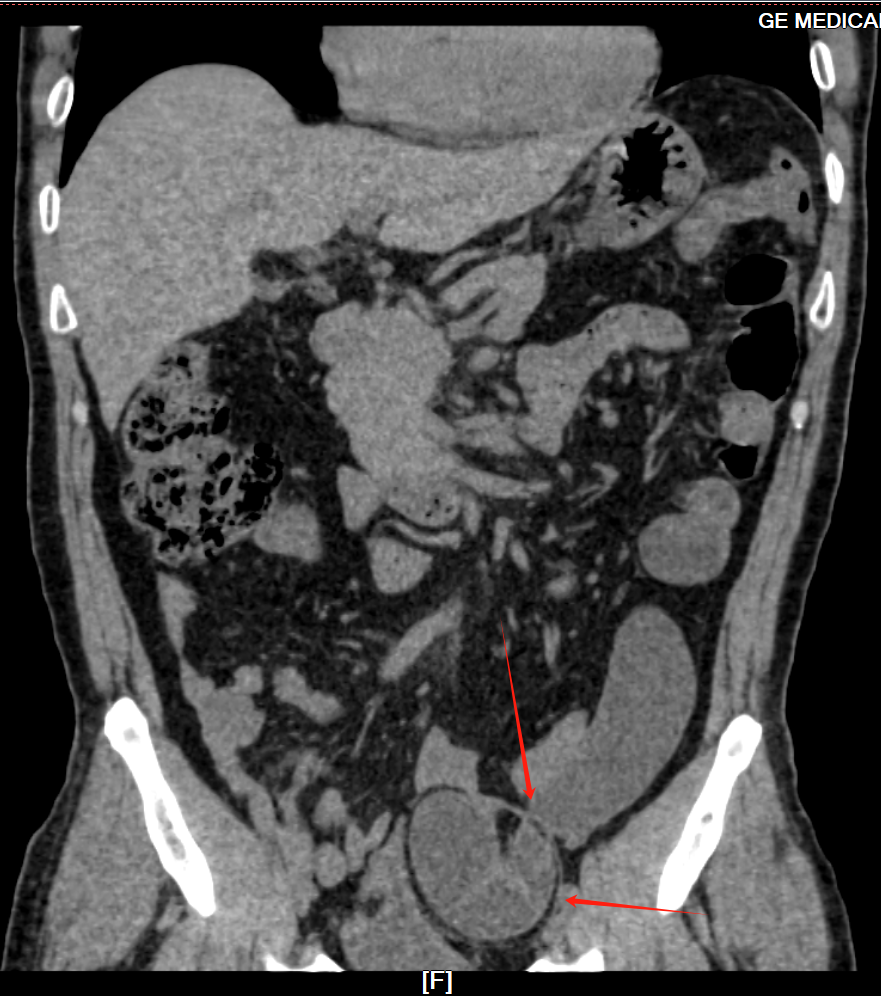

经过外科团队的进一步检查,明确了“左侧嵌顿性腹股沟直疝”的诊断(患者情况紧急,如不及时处理,可能引发肠缺血、坏死等严重后果。)